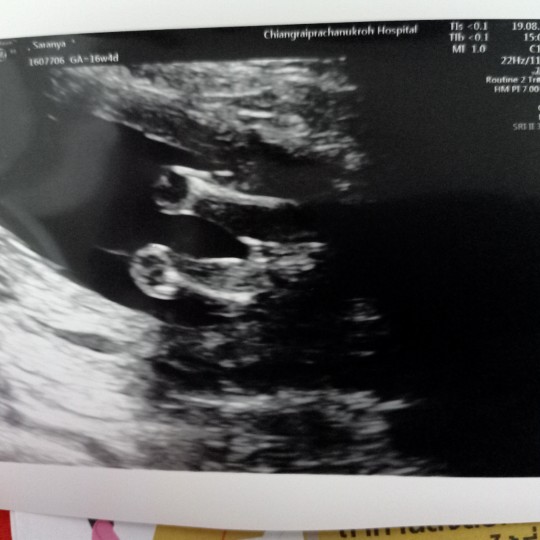

หนูมีกลีบค้าา😂

กลีบเต็มๆคะ